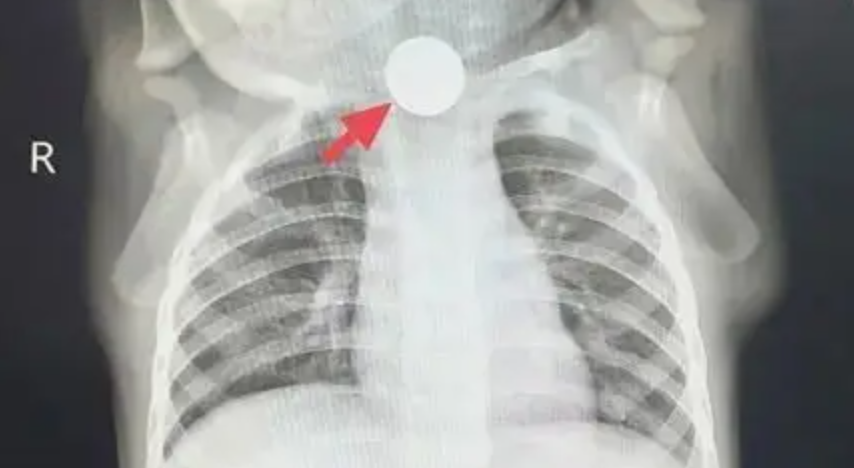

“Không thể chủ quan được, trước tiên cho bé chụp X-quang ngực để loại trừ vấn đề ở phổi!” – bác sĩ dặn gia đình. Thế nhưng, kết quả phim chụp mang lại không phải sự yên tâm, mà là một phát hiện khiến mọi người giật mình: ở đoạn trên thực quản của Đông Đông, có một đồng xu mắc kẹt!

Sự thật lập tức sáng tỏ: cái gọi là “chán ăn” thực chất là đồng xu mắc ở thực quản gây đau, khiến bé không thể ăn uống bình thường; chảy nước dãi là do dị vật chặn lại, nước bọt không nuốt xuống được; ho là phản xạ khi nước bọt tràn vào đường thở. Chẩn đoán trước đó là “chán ăn do ảnh hưởng tâm lý” hoàn toàn là nhận định sai lầm!

“Trẻ bị mắc một đồng xu trong thực quản đã gần một tuần, cần chuẩn bị nội soi lấy dị vật ngay!”. Sau khi nhận được thông báo khẩn, ê-kíp nội soi nhanh chóng vào vị trí, chuẩn bị kỹ lưỡng trước thủ thuật. Khi ống nội soi dạ dày được đưa vào, có thể thấy rõ đồng xu mắc ngang trong thực quản. Vùng niêm mạc xung quanh đã bị viêm đỏ, sưng phù, thậm chí xuất hiện ổ loét sâu, liên tục rỉ máu. Các bác sĩ thao tác hết sức cẩn trọng, chính xác gắp lấy đồng xu. Toàn bộ quá trình diễn ra trong không khí căng thẳng nhưng trật tự, cuối cùng đồng xu cũng được lấy ra thành công. Nhìn đồng xu vừa được gắp ra, bố mẹ Đông Đông vừa đau lòng vừa nhẹ nhõm, liên tục nắm tay bác sĩ cảm ơn.